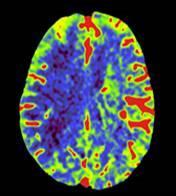

Oncology risk prediction Brain tumor and mets

Lung cancer screening Chest CT Pulmonary lesions – Chest X-Ray

Supports 200+ organs at risk + clinical target volumes. 1000+ sites, 1.2M cancer patients / year

• Includes lymph node stations in Pelvic, Head & Neck, and Breast Cancer

• 82% time savings